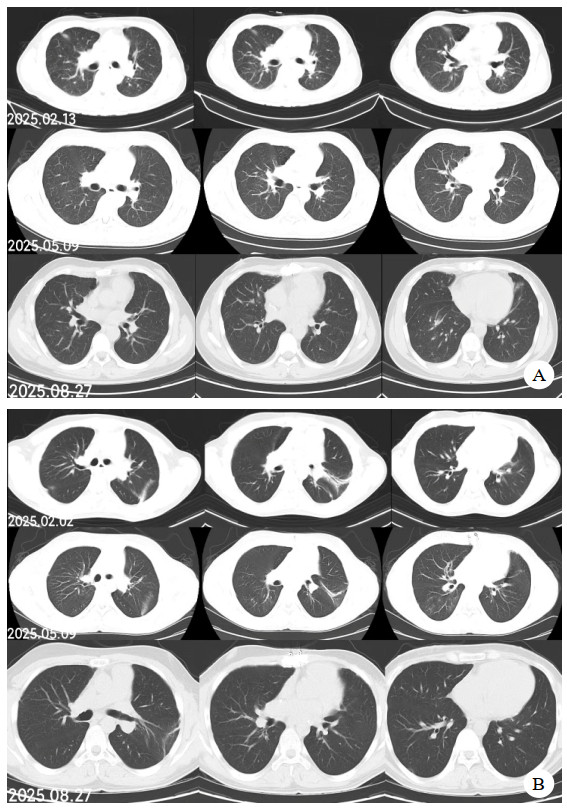

| 注:图A为B某;图B为C某 图 7 肺移植术后第2个月、5个月、8个月CT影像 |

同时给予镇痛、镇静联合肌松,去甲肾上腺素泵入维持血压,俯卧位通气,B某入院后出现高热,经验性给予美罗培南联合万古霉素抗感染治疗,后降阶梯调整为哌拉西林他唑巴坦联合万古霉素治疗;C某抗感染方案为经验性使用万古霉素联合哌拉西林他唑巴坦治疗,痰培养出鲍曼不动杆菌后改为替加环素、头孢哌酮舒巴坦及万古霉素治疗;根据《刺激性气体中毒诊治专家共识》[5]中关于重症患者的治疗措施,同时给予2人泮托拉唑抑酸护胃,氨溴索、富露施化痰、甲泼尼龙抗炎、西维来司他纳及乌司他丁清除炎性介质,维生素C抗氧化、保肝、输血补液,纤支镜吸痰及肺泡灌洗,维持水电解质平衡及营养支持治疗,特别考虑到肺损伤情况,在使用有创通气时给予超保护性通气策略[5, 7];2人仍先后出现气胸、纵膈气肿,行胸腔闭式引流;持续V-V ECMO治疗15 d后,肺部纤维化不可逆转,高分辨率CT肺纤维化评分 > 75%(图 3、4),符合终末期肺病标准,有肺移植指征[8],经评估后2人顺利完成病变肺组织切除(图 5),双侧序贯肺移植,术后患者复查胸片肺部恢复正常(图 6),2位患者术后气管切管接呼吸机辅助通气,并给予泼尼松、他克莫司、吗替麦考酚酯抗排异治疗,其余根据病情给予万古霉素调节肠道菌群、抗感染、保肝、抗凝、呼吸康复锻炼等治疗,后顺利脱机、拔除气切套管,病情稳定出院,后续规律复查胸部CT(图 7)恢复良好。